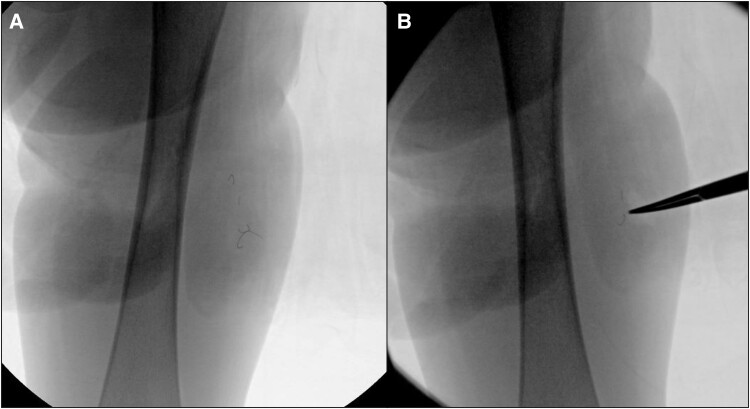

A 2-year-old male with genetic-negative, diazoxide-responsive hyperinsulinism presented with a knot in his left, lateral thigh. His hypoglycemia was managed with diazoxide, chlorothiazide, and monitoring via a Dexcom G6 continuous glucose monitor (CGM). X-ray showed 3 metallic wire foreign bodies, consistent with retained Dexcom sensor wires. He was referred to surgery for foreign body removal. Intraoperative fluoroscopy revealed 4 pieces of wire. Two superficial pieces were removed, but 2 small pieces deep to the fascia remained because of significant risk of injury or bleeding if removal was attempted. We present this case to increase awareness in the literature regarding retention of CGM wires. Raised nodules at sites of CGM insertion without fluctuation or erythema and persistent pain should raise suspicion for retention of sensor wires.

2岁男性,遗传阴性,二氮卓反应性高胰岛素症表现为左外侧大腿结。患者使用二氮氧化物、氯噻嗪治疗低血糖,并通过Dexcom G6连续血糖监测仪(CGM)进行监测。x线显示3个金属丝异物,与保留的Dexcom传感器丝一致。他被转到外科做异物取出手术。术中透视显示4根钢丝。两个表面的碎片被移除,但2个深至筋膜的小碎片仍然存在,因为如果试图移除,有很大的受伤或出血风险。我们提出这个病例是为了提高文献中对CGM金属丝潴留的认识。CGM插入部位隆起结节,无波动或红斑和持续疼痛,应怀疑传感器导线保留。